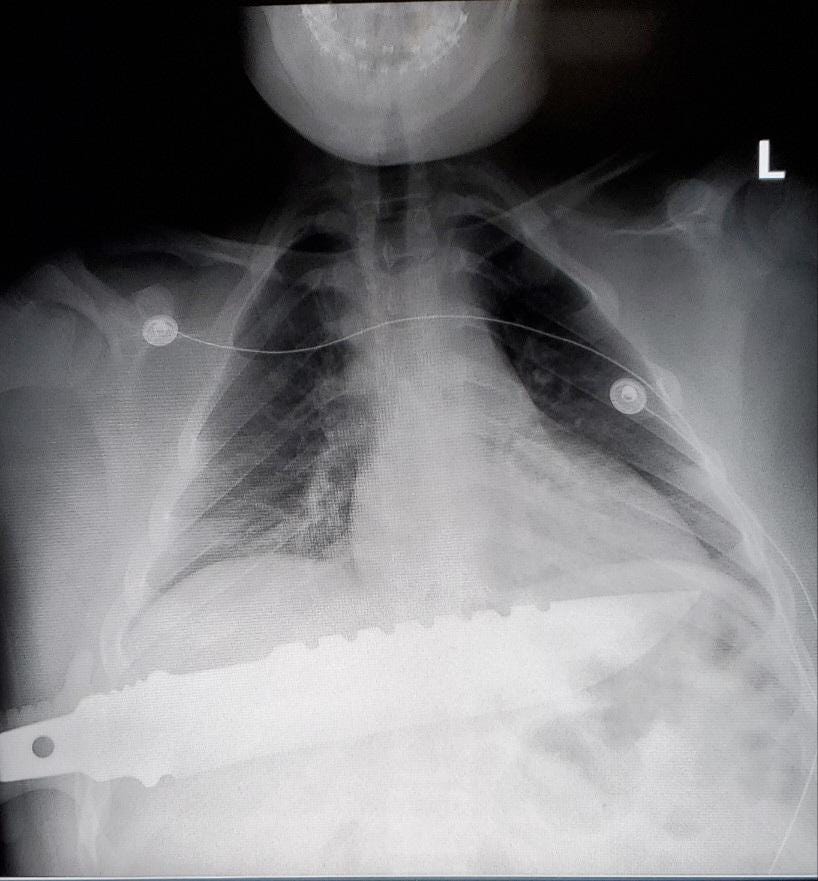

X-ray of a 13 year old… Yes, it missed all the important stuff inside…